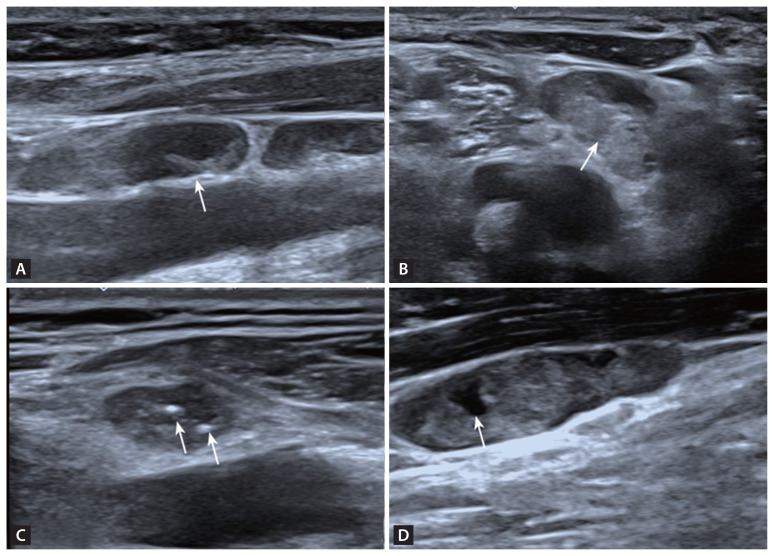

背景/目的:本研究旨在利用多模态超声参数建立一个诊断模型,以帮助检测甲状腺乳头状癌(PTC)患者的颈淋巴结转移:研究对象包括 69 名 PTC 患者的 84 个可疑淋巴结,所有患者均接受了细针穿刺,并获得了病理结果。研究分析了传统灰阶超声、剪切波弹性成像(SWE)和超微血管成像的数据。通过比较良性组和转移组的主要超声特征,利用费雪逐步判别分析建立了一个诊断模型。通过自我测试、交叉验证和接收器操作特征曲线分析评估了模型的有效性:淋巴结(X1)、皮质高回声(X2)、血管形态(X4)和 SWEmean(X7)这四个特征是判别分析中不可或缺的部分,并得出以下等式:Y1 = -3.461 + 2.423x1 + 0.321x2 + 1.620x4 + 0.109x7,Y2 = -8.053 + 0.414x1 + 2.600x2 + 2.504x4 + 0.192x7。如果 Y1 < Y2,该淋巴结将被诊断为转移性淋巴结。该模型的曲线下面积为 0.833,灵敏度为 83.33%,特异度为 83.33%:通过费雪逐步判别分析建立的多模态超声诊断模型证明能有效识别 PTC 患者的转移性淋巴结。

Methods: The study included 84 suspicious lymph nodes from 69 PTC patients, all of whom underwent fine needle aspiration with pathological results. Data from conventional grayscale ultrasound, shear wave elastography (SWE), and superb microvascular imaging were analyzed. Key ultrasound features were compared between benign and metastatic groups to create a diagnostic model using Fisher's stepwise discriminant analysis. The model's effectiveness was assessed with self-testing, cross-validation, and receiver operating characteristic curve analysis.